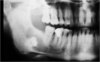

Figure 1 & 2 : lorsque les racines sont matures comme cela, imaginez le délabrement osseux nécessaire !

Figure 3 : kyste sur dent de sagesse non évoluée.

Figure 4 : carie et délabrement de la mollaire de 12 ans lors de l'éruption de la dent de sagesse.